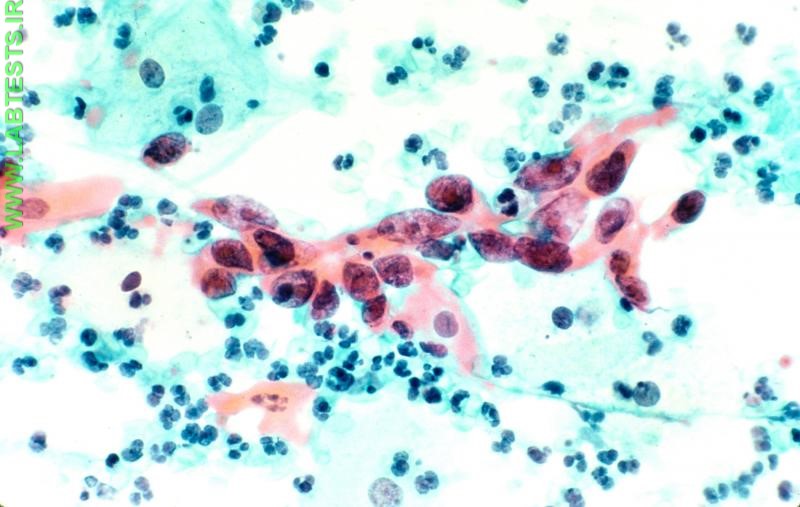

• Pap test: the Papanicolaou (Pap) test is widely used to screen for precancerous or cancerous changes in cervical cells. The earliest, precancerous changes cause the cells lining the inside or outside of the cervix to appear different from normal cervical cells. These changes, when present on a Pap test, are termed "atypical cells." Atypical cells are not entirely specific for a precancerous condition, however, and can temporarily appear in response to infections or irritation of the cervix lining. Precancerous cells can become more abnormal in appearance over time and are more likely to progress to cancer if left untreated. In Pap tests, these more abnormal (intermediate) cellular changes are called low-grade or high-grade squamous intraepithelial lesions [see the sidebar on Pap test terminology].